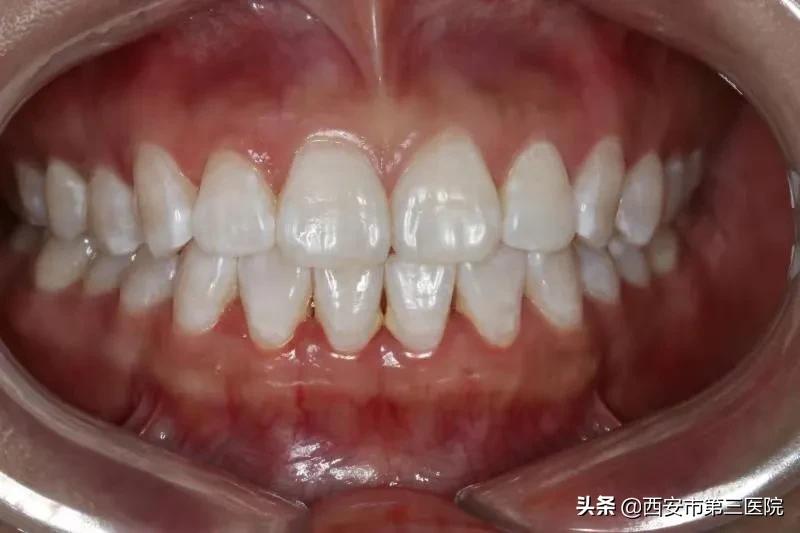

二、皓齿美白

具有高效快速、保护牙齿、舒适无痛、效果持久 等优点。皓齿美白技术通过氧化剂过氧化氢中的小分子,穿过牙釉质和牙本质渗透到牙齿的所有部分,在釉小柱间移动,分解清除牙变色的色素分子,15分钟就能产生美白作用。

美白前

美白后